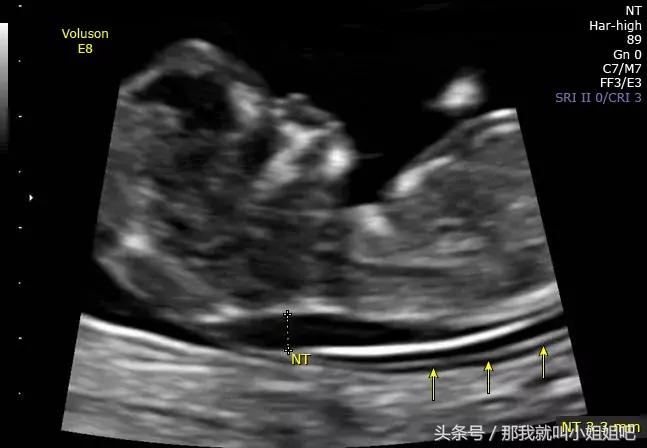

下图即为一例孕12周胎儿NT增厚(NT=3.3mm)的超声影像表现:

(图片来源:uptodate)

NT增厚的胎儿,可能存在染色体异常,包括21-三体综合征、18-三体综合征、13-三体综合征、45X(Turner’s综合征)等。NT越厚,胎儿染色体异常的风险越大。

此外,胎儿还可能存在淋巴系统发育异常、先天性心脏病等,流产、胎儿死亡的风险也因此升高。